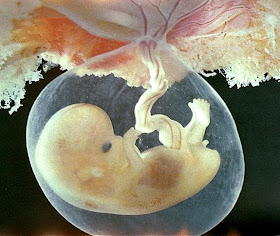

6 haftalık bebeğin görüntüsü nasıldır?

| görüntü 2 |